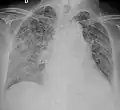

Miliary tuberculosis is a form of tuberculosis that is characterized by a wide dissemination into the human body and by the tiny size of the lesions (1–5 mm). Its name comes from a distinctive pattern seen on a chest radiograph of many tiny spots distributed throughout the lung fields with the appearance similar to millet seeds—thus the term "miliary" tuberculosis. Miliary TB may infect any number of organs, including the lungs, liver, and spleen.[2] Miliary tuberculosis is present in about 2% of all reported cases of tuberculosis and accounts for up to 20% of all extra-pulmonary tuberculosis cases.[3]

| Chest X ray showing miliary tuberculosis | |

Testing for miliary tuberculosis is conducted in a similar manner as for other forms of tuberculosis, although a number of tests must be conducted on a patient to confirm diagnosis.[4] Tests include chest x-ray, sputum culture, bronchoscopy, open lung biopsy, head CT/MRI, blood cultures, fundoscopy, and electrocardiography.[10] The tuberculosis (TB) blood test, also called an Interferon Gamma Release Assay or IGRA, is a way to diagnose latent TB. A variety of neurological complications have been noted in miliary tuberculosis patients—tuberculous meningitis and cerebral tuberculomas being the most frequent. However, a majority of patients improve following antituberculous treatment. Rarely lymphangitic spread of lung cancer could mimic miliary pattern of tuberculosis on regular chest X-ray. [15]